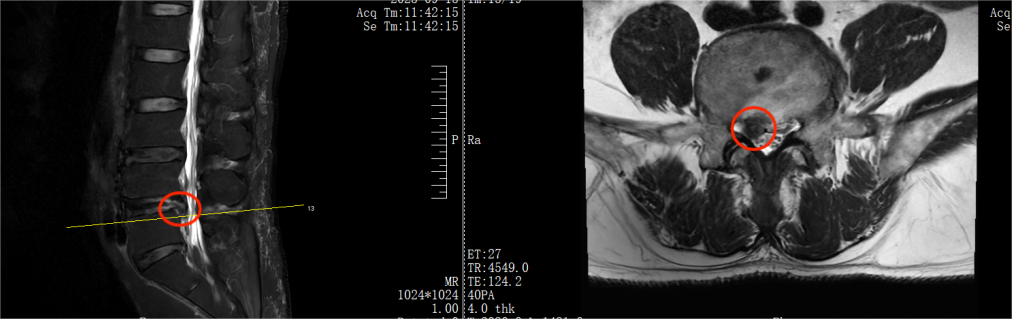

67 岁的胡叔叔,因长期在家行重体力劳作,一年前出现右腿放射性疼痛、麻木,从腰部窜至大腿后外侧、小腿外侧及足背,久坐、久站、弯腰时疼痛加剧,虽然进行了规范的保守治疗,但症状依然断断续续,近半年又再次加重,无法正常行走,无法直立。经腰椎 MRI 检查,确诊为 L4/5 椎间盘突出(脱出),突出的髓核组织压迫了神经根。

术前影像

DR:腰椎退行性改变

CT:L4/5 椎间盘突出(偏右侧)

MRI:L4/5 椎间盘突出,L4/5 层面椎管狭窄

术后影像